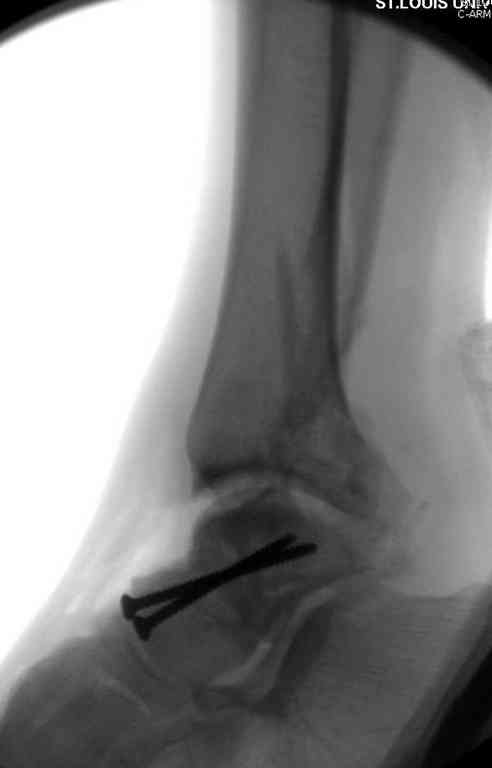

Здесь на фото примеры:

Переломовывих тарана с повреждением медиальной стороны. Через 4 часа после поступления проведена репозиция и фиксация тарана после Irrigation&Debridment. Частичное несращение медиальной лодыжки не беспокоит, вернулся к активному образу жизни. Полная нагрузка разрешена через 11 недель. Финальные снимки через 11 месяцев.

Второй случай прооперирован вчера.

10 дней назад поступил с открытым повреждением медиальной лодыжки и переломо вывихом таранной кости. Ургентно сделана репозиция с наложением наружного фиксатора + Irrigation&Debridment.

Во время репозиции выявили повреждение заднего сухожилия м. тибиалис и задней большеберцовой артерии. Медиальную рану удалось закрыть частично и установлен вакуум.

Дважды провели Irrigation&Debridment с заменой вакуума.

Вчера провели фиксацию.

Из-за многооскольчатости дистальной части малоберцовой, где невозможно было провести фиксацию шурупами, перелом зафиксирован подпирающей пластиной, которая должна служить дополнением отсутствующей дистальной части малоберцовой (lateral cortex substitute).

Для стабильности два шурупа на синдесмоз.

Медиальную рану с приближенными краями продолжаем вакуумировать (KCI). Наружный фиксатор оставлен на пару недель, надеюсь, небольшая рана будет гранулировать и закроется без кожной пластики. Фиксация медиальной ложыжки не планируется.